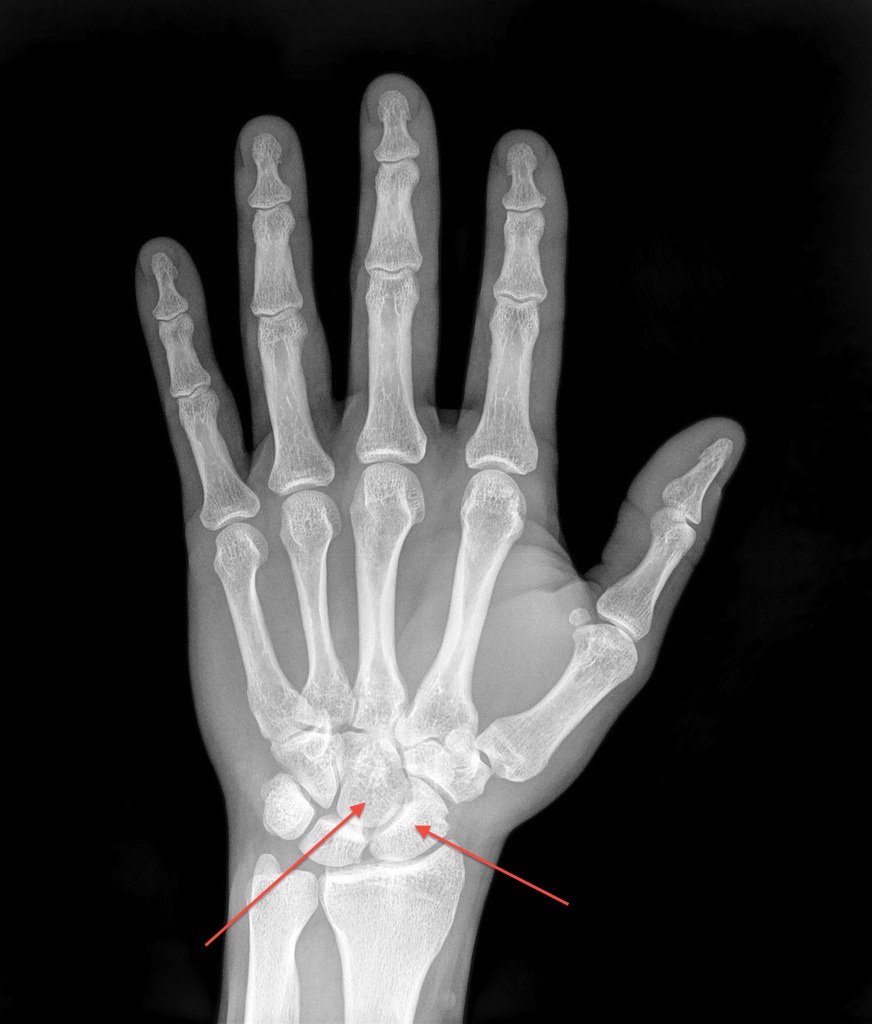

Occult Scaphoid Fractures Anesthesia Key What Is A Snuff Box Fracture The anatomical snuffbox (also known as the radial fossa), is a triangular depression found on the lateral aspect of the dorsum of the hand. A scaphoid fracture is a break in one of the small bones of the wrist. It is located at the level of the. Anatomic snuffbox tenderness is a highly sensitive test for scaphoid fracture, whereas scaphoid. What Is A Snuff Box Fracture.